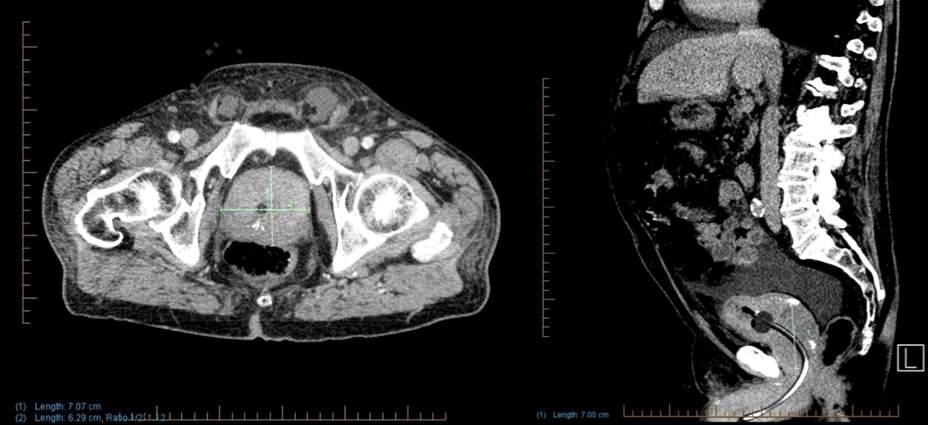

Issuu converts static files into: digital portfolios, online yearbooks, online catalogs, digital photo albums and more. Sign up and create your flipbook.